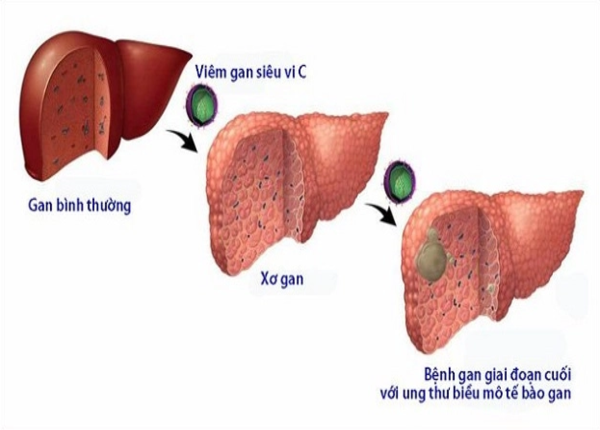

Viêm gan C là một trong những bệnh lý gan truyền nhiễm phổ biến và nguy hiểm hiện nay. Căn bệnh do virus HCV gây ra, có khả năng tấn công trực tiếp vào tế bào gan, gây viêm mạn tính và phá hủy cấu trúc gan dần theo thời gian. Bệnh thường diễn tiến âm thầm, không có triệu chứng rõ ràng ở giai đoạn đầu, khiến nhiều người chỉ phát hiện khi bệnh đã tiến triển có dấu hiệu xơ gan hoặc biến chứng nặng như ung thư gan.

Quá trình viêm kéo dài làm tế bào gan bị tổn thương và dần bị thay thế bởi mô xơ (sẹo). Mô xơ này gây cản trở lưu thông máu trong gan, giảm khả năng trao đổi chất, thải độc và tổng hợp protein. Khi mô xơ lan rộng, gan mất dần chức năng, dẫn đến xơ gan, tuy nhiên điều trị đúng cách vẫn có thể làm chậm tiến triển của bệnh.

Có khoảng 20–30% người bị viêm gan C mạn tính có thể tiến triển thành xơ gan sau 20–30 năm, tùy vào cơ địa và các yếu tố nguy cơ kèm theo như uống rượu, béo phì, nhiễm đồng thời HBV hoặc HIV, hay sử dụng thuốc gây độc cho gan kéo dài.

Viêm gan C là một trong những nguyên nhân hàng đầu dẫn đến xơ gan và ung thư gan nguyên phát trên thế giới. Tình trạng viêm gan kéo dài không được điều trị khiến gan bị tổn thương mạn tính, khả năng tái tạo tế bào gan suy giảm, và quá trình xơ hóa diễn ra nhanh hơn.

Khoảng 70–80% bệnh nhân ung thư gan có nền tảng là xơ gan, trong đó một phần lớn liên quan đến viêm gan C kéo dài không được điều trị. Khi gan mất khả năng thải độc và tổng hợp protein, cơ thể sẽ gặp rối loạn chuyển hóa, suy kiệt và dễ dẫn đến biến chứng nguy hiểm.